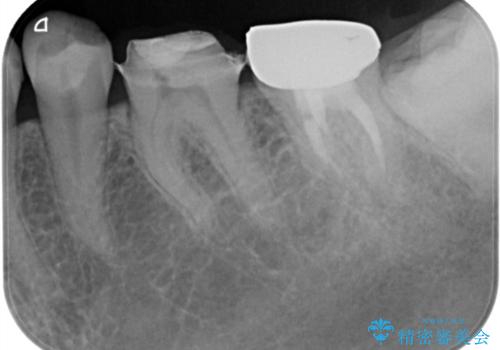

- 他院で、仮歯にしたがセラミックの値段が高すぎると思ったため治療相談も含めて来院された患者様です。

仮歯を新調させていただき、再度虫歯治療を行なって、歯の形を作りセラミックを入れさせていただきました。

フルジルコニアクラウン 7万円(税抜)

仮歯 1万円